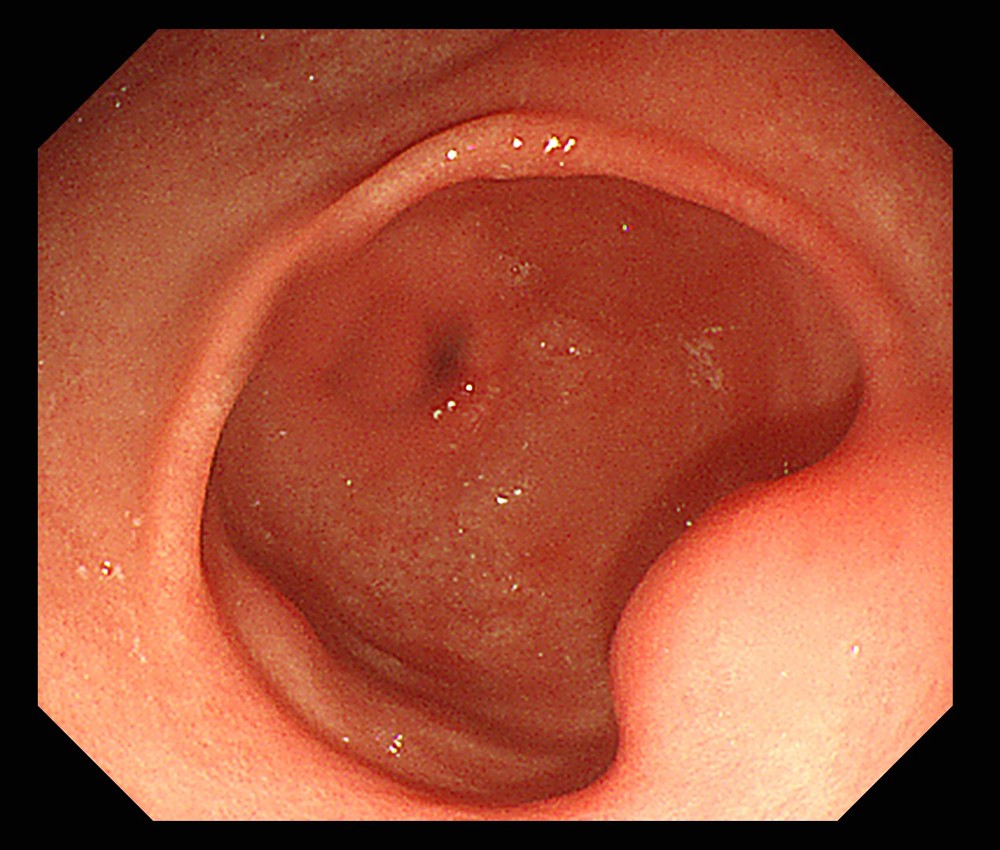

48岁的张先生在一次胃镜检查中发现胃窦部有一处隆起性病变,性质不明。是常见的异位胰腺(一种无需处理的正常组织变异)?还是需要手术处理的间质瘤?单纯胃镜难以判断。

为此,张先生在医院接受了超声内镜检查。脾胃病科副主任医师景洪海检查发现,该隆起来源于黏膜下层,呈偏低回声,内部结构不均,但周围胃壁层次清晰正常。结合其顶端有凹陷的特征,超声内镜明确提示“异位胰腺考虑”。

这个结论意味着张先生无需任何手术或特殊治疗,只需定期随访观察即可。一次精准的检查,成功化解了患者的焦虑,也避免了过度医疗。